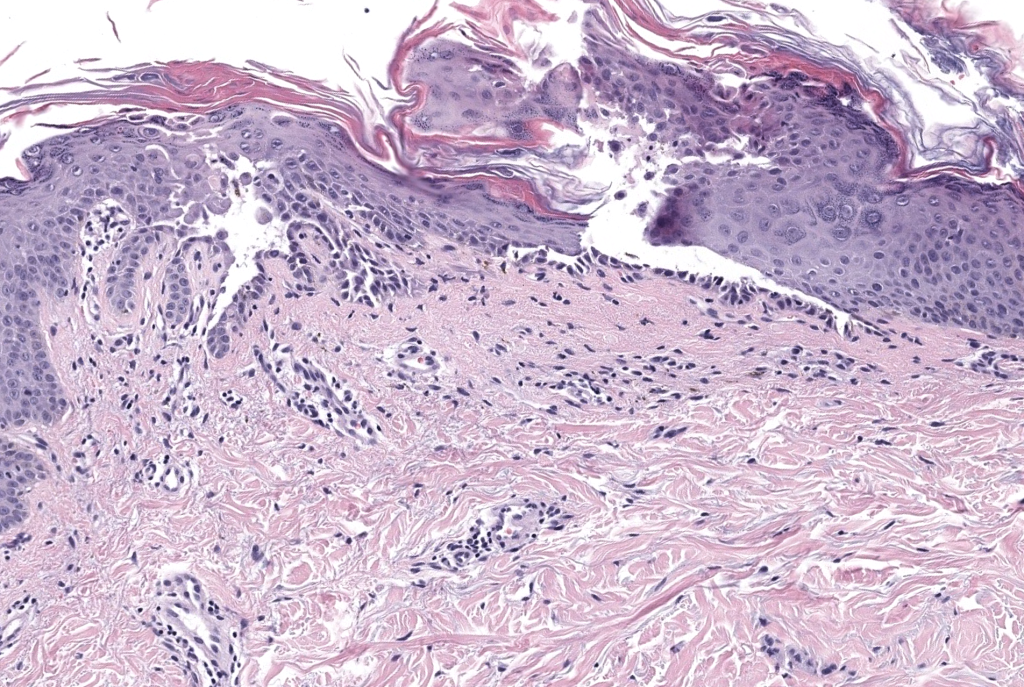

- Histología: acantólisis focal en epidermis superior con o sin disqueratosis; posible mezcla de patrones tipo Darier/Hailey-Hailey/pénfigo Davis 1999.